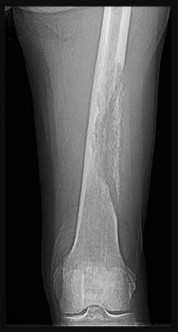

Figures 9a through 9d are the anteroposterior and lateral radiographs, CT scan, and technetium bone scan of a 12-year-old boy who has experienced 7 months of pain in his lower leg. The pain limits his ability to participate in sports and he is having difficulty sleeping. He is afebrile, and laboratory study findings including an erythrocyte sedimentation rate, C-reactive protein, and complete blood count are within normal limits.

The images and clinical history support a diagnosis of osteoid osteoma, which most commonly occurs in adolescence. Although these lesions can be seen in any bone, they are usually located in the femur and tibia. The significant inflammatory response to this tumor is secondary to high levels of prostaglandin production. Characteristic night pain is relieved with nonsteroidal anti-inflammatory drugs (NSAIDs) or by aspirin.

Radiographic images show thickened bone and a small central nidus. Thin-cut CT scan is the imaging of choice to visualize the nidus. A bone scan is associated with uptake but is not specific. Treatment options include expectant management with NSAIDs and observation under the premise that these lesions eventually burn out. Contemporary treatment involves RFA. Historically, these lesions were treated with en bloc resection; however, this technique has largely fallen out of favor because of the high efficacy and comparative low morbidity associated with RFA.

When an osteoid osteoma occurs in the spine, it is located in the posterior elements, and paraspinal pain and scoliosis often are present.